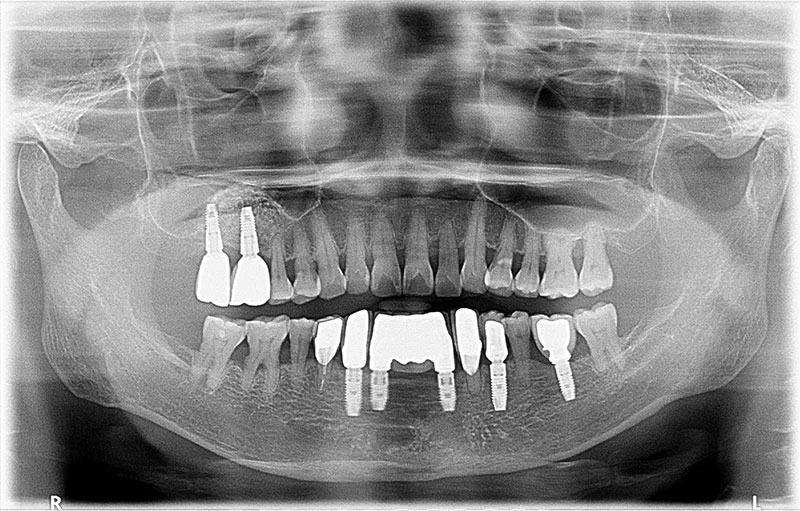

術前

術後